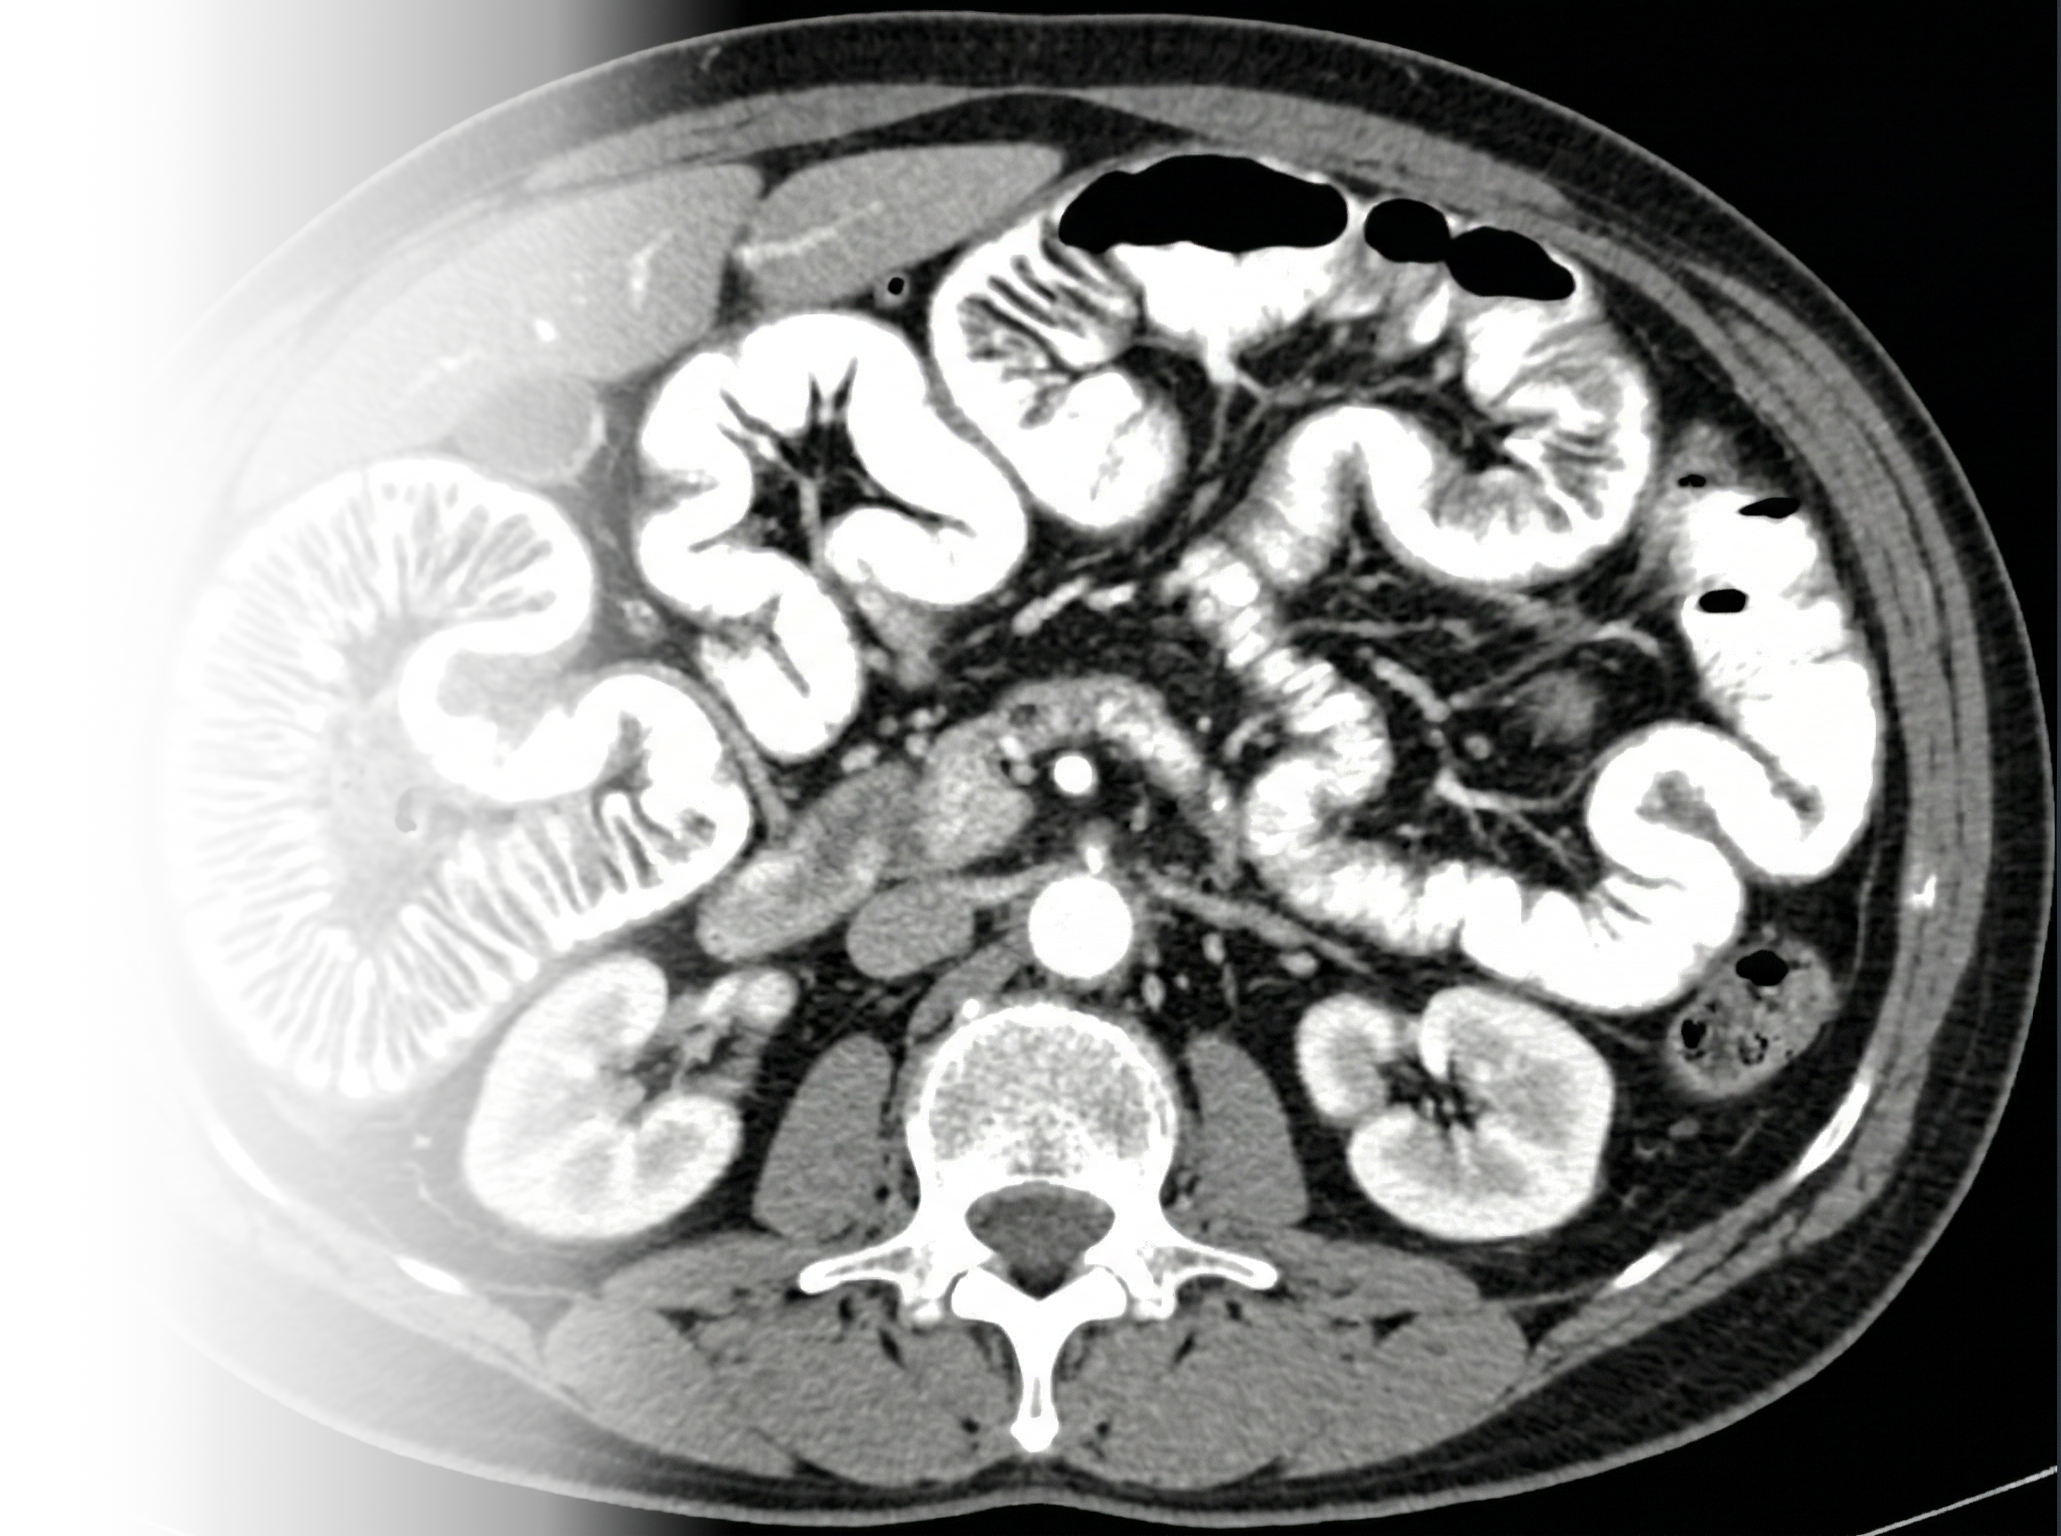

МСКТ энтерография с контрастным усилением является одним из передовых методов диагностики заболеваний желудочно-кишечного тракта, позволяющих детально изучить состояние тонкой кишки. Этот метод сочетает преимущества компьютерной томографии (КТ) с использованием специального контраста, что обеспечивает высокую точность и информативность получаемых изображений.

КТ энтерография представляет собой высокотехнологичный процесс, который позволяет получать трёхмерные изображения тонкой кишки. В отличие от традиционных рентгеновских исследований, МСКТ обеспечивает детальное визуальное отображение анатомических структур, выявляя даже незначительные изменения. Контрастное усиление в данном случае играет ключевую роль: оральный контрастный раствор, состоящий из вещества, хорошо различимого на КТ, равномерно заполняет просвет тонкой кишки, выделяя её границы и позволяя выявить патологические процессы.